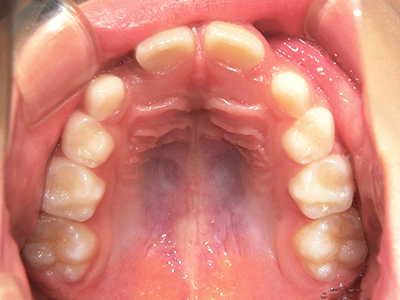

↓ - 頬の圧力が上の歯列にかかりやすくなる

↓ - 上あごが狭くなる

ないき歯科クリニックでは、上あごの成長不足を補い、鼻呼吸を獲得しつつ歯列を整え、将来のお口をより健康な状態にすることをゴールに定める矯正治療をおこなっています。